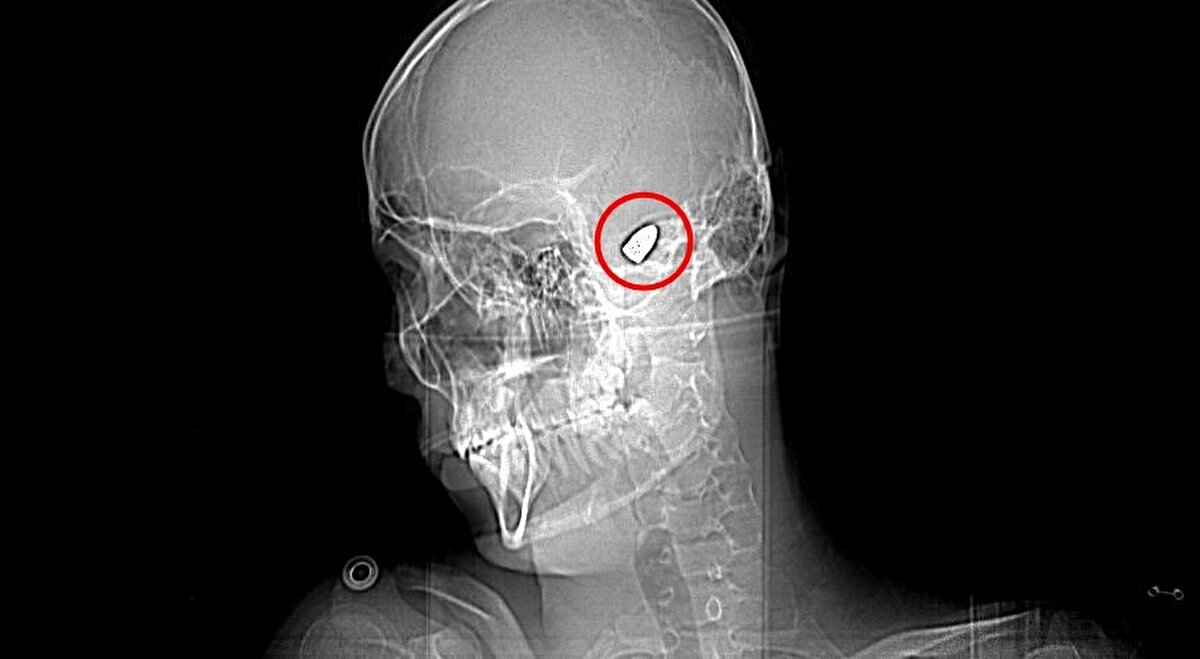

Olay, 5 Kasım 2023’te Bahçelievler Mahallesi 1624'üncü Sokak'ta meydana geldi. Arkadaşları ve ağabeyiyle maça gitmek için evinden çıkan Yusuf Emre Özbek, birlikte fotoğraf çektirdikten hemen sonra yere yığıldı. Çevredekilerin hastaneye götürdüğü Yusuf’un çekilen röntgeninde, başında mermi çekirdeği olduğu tespit edildi. 4 gün yoğun bakım, 4 gün de serviste tedavi gören Yusuf’un başındaki mermi için doktorlar, riskli bölgede olduğu gerekçesiyle müdahale etmedi. Düzenli olarak kontrol edilen Yusuf’ta konuşma güçlüğü ve sağ el ve parmaklarında zayıflık belirtileri ortaya çıkınca, fizik tedavi süreci başladı.

Halen sağ elini kullanmakta ve parmaklarımı oynatmakta zorlanan Yusuf, ölüm korkusu yaşadığını belirterek, "Hastanede başıma yorgun mermi isabet ettiği tespit edildi. Mermi riskli bir yerde olduğu için doktorlar çıkarılamayacağını söylediler. O andan itibaren benim için çok zorlu bir süreç başladı. Ellerimi hareket ettirmekte, yürümekte ve konuşmakta zorluk çekiyordum. 1,5 yıl boyunca yoğun bir fizik tedavi dönemin oldu.

Bu süre sonunda bazı iyileşmeler oldu ama hala sağ elimi kullanmakta özellikle de parmaklarımı oynatmakta zorlanıyorum. Şu anda okuluma ve sosyal hayatıma dönebildim. Kafamda bir mermi ile yaşadığım için ölüm korkusu yaşıyorum. Sürekli bir tedirginlik içerisindeyim. Bu 1,5 yıl boyunca ailem ve arkadaşlarım bana çok destek oldular. Onlar da benim kadar çabaladı. Buradan vatandaşlarımıza bir uyarıda bulunmak istiyorum. Lütfen rastgele havaya ateş açmayın. Rastgele sıkılan bir kurşun başkasının hayatını karartabilir. Benim hayatımı karartan kurşunu sıkanların yakalanmasını istiyorum" dedi.